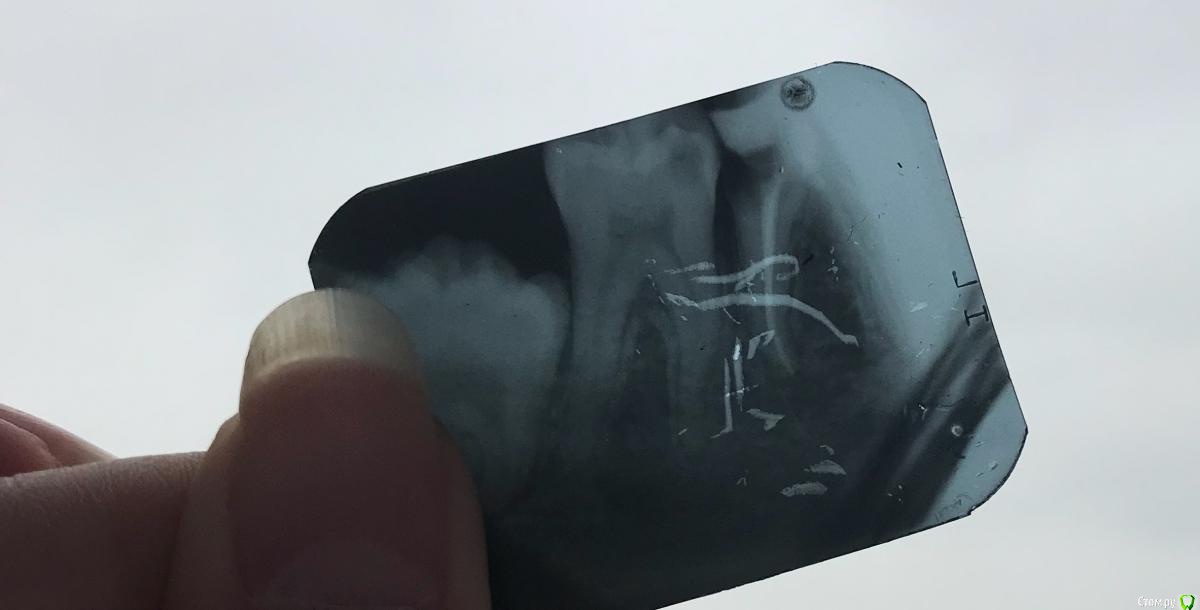

AnnaMatse Опубликовано 29 января, 2018 Автор Поделиться Опубликовано 29 января, 2018 сделала пока только прицельный снимок того зуба , который болит при нажатии. Не могу редактировать запись и добавить его, не вижу кнопки « изменить» Ссылка на комментарий

AnnaMatse Опубликовано 29 января, 2018 Автор Поделиться Опубликовано 29 января, 2018 Вот , правда он поцарапался, не знаю как это произошло..достала из чехла, а он такой. Ссылка на комментарий